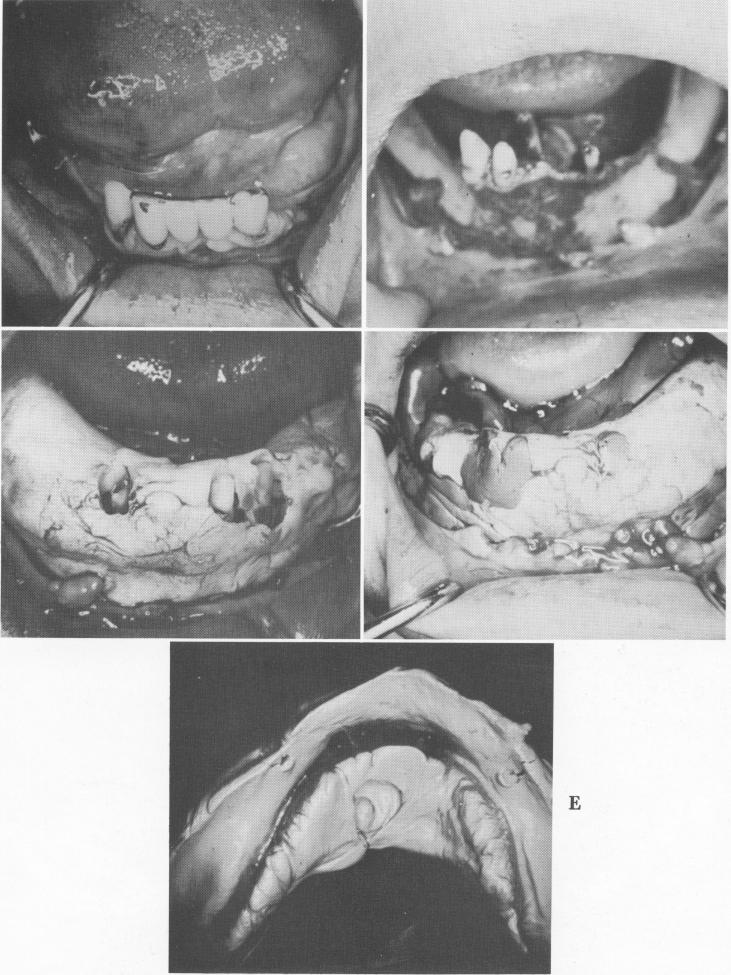

The following case clearly illustrates the technique. Only three anterior teeth remained; these sup-ported a five-unit splint (Fig. 12-101, A).

The remaining anterior teeth were prepared for full crown restorations. It was necessary to eliminate

Fig. 12-101. A, Only three teeth supported the anterior splint. B, The abutment teeth were pre-pared for full crown restorations and the tissue retracted to expose the bone. C, A cold cure acrylic tray was molded to the exposed bony landmarks. D, A rubber base impression was taken. E, The impression also included the three tooth impressions.